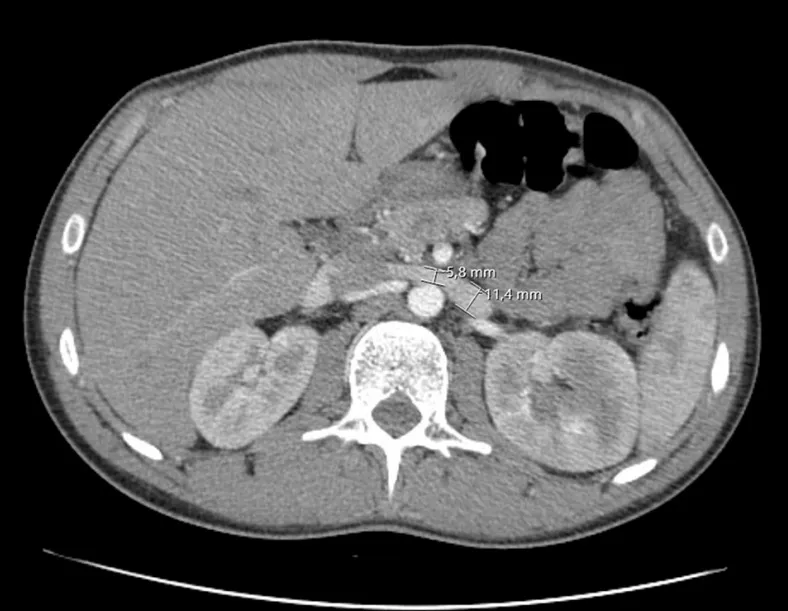

IRA + Icterícia: Um Caso que Exige Investigação Detalhada